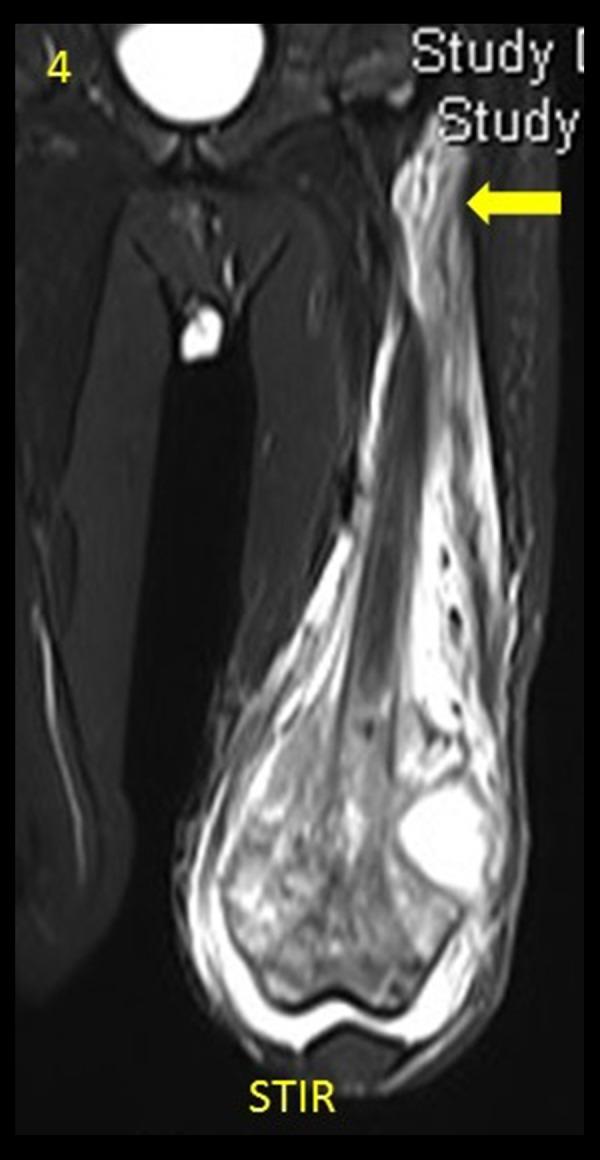

It is imperative that bone tumour margin and extent of tumour involvement are accurately assessed pre-operatively in order for the surgeon to attain a safe surgical margin. In this study, we comprehensively assessed each of the findings that influence surgical planning, on various MRI sequences and compared them with the gold standard - pathology.

MATERIAL/METHODS: In this prospective study including 21 patients with extremity bone tumours, margins as seen on various MRI sequences (T1, T2, STIR, DWI, post-gadolinium T1 FS) were measured and biopsies were obtained from each of these sites during the surgical resection. The resected tumour specimen and individual biopsy samples were studied to assess the true tumour margin. Margins on each of the MRI sequences were then compared with the gold standard - pathology. In addition to the intramedullary tumour margin, we also assessed the extent of soft tissue component, neurovascular bundle involvement, epiphyseal and joint involvement, and the presence or absence of skip lesions.

T1-weighted imaging was the best sequence to measure tumour margin without resulting in clinically significant underestimation or overestimation of the tumour extent (mean difference of 0.8 mm; 95% confidence interval between -0.9 mm to 2.5 mm; inter-class correlation coefficient of 0.998). STIR and T1 FS post-gadolinium imaging grossly overestimated tumour extent by an average of 16.7 mm and 16.8 mm, respectively (P values <0.05). Post-gadolinium imaging was better to assess joint involvement while T1 and STIR were the best to assess epiphyseal involvement.

T1-weighted imaging was the best sequence to assess longitudinal intramedullary tumour extent. We suggest that osteotomy plane 1.5 cm beyond the T1 tumour margin is safe and also limits unwarranted surgical bone loss. However, this needs to be prospectively proven with a larger sample size.

为使外科医生获得安全的手术切缘,术前准确评估骨肿瘤的边界和肿瘤累及范围至关重要。在本研究中,我们全面评估了各种MRI序列上影响手术规划的各项发现,并将其与金标准——病理结果进行比较。

材料/方法:在这项前瞻性研究中,纳入了21例四肢骨肿瘤患者,测量了各种MRI序列(T1、T2、短TI反转恢复序列(STIR)、扩散加权成像(DWI)、钆增强T1脂肪抑制序列(T1 FS))上所见的边界,并在手术切除过程中从每个部位获取活检样本。对切除的肿瘤标本和各个活检样本进行研究,以评估真正的肿瘤边界。然后将每个MRI序列上的边界与金标准——病理结果进行比较。除了评估髓内肿瘤边界外,我们还评估了软组织成分的范围、神经血管束受累情况、骨骺和关节受累情况以及跳跃性病变的有无。

T1加权成像在测量肿瘤边界方面是最佳序列,不会导致对肿瘤范围的临床显著低估或高估(平均差异为0.8mm;95%置信区间为-0.9mm至2.5mm;组内相关系数为0.998)。钆增强后的STIR和T1 FS成像分别平均高估肿瘤范围16.7mm和16.8mm(P值<0.05)。钆增强成像在评估关节受累方面更佳,而T1和STIR在评估骨骺受累方面最佳。

T1加权成像在评估纵向髓内肿瘤范围方面是最佳序列。我们建议在T1肿瘤边界以外1.5cm处进行截骨是安全的,并且还能限制不必要的手术骨质丢失。然而,这需要通过更大样本量的前瞻性研究来证实。